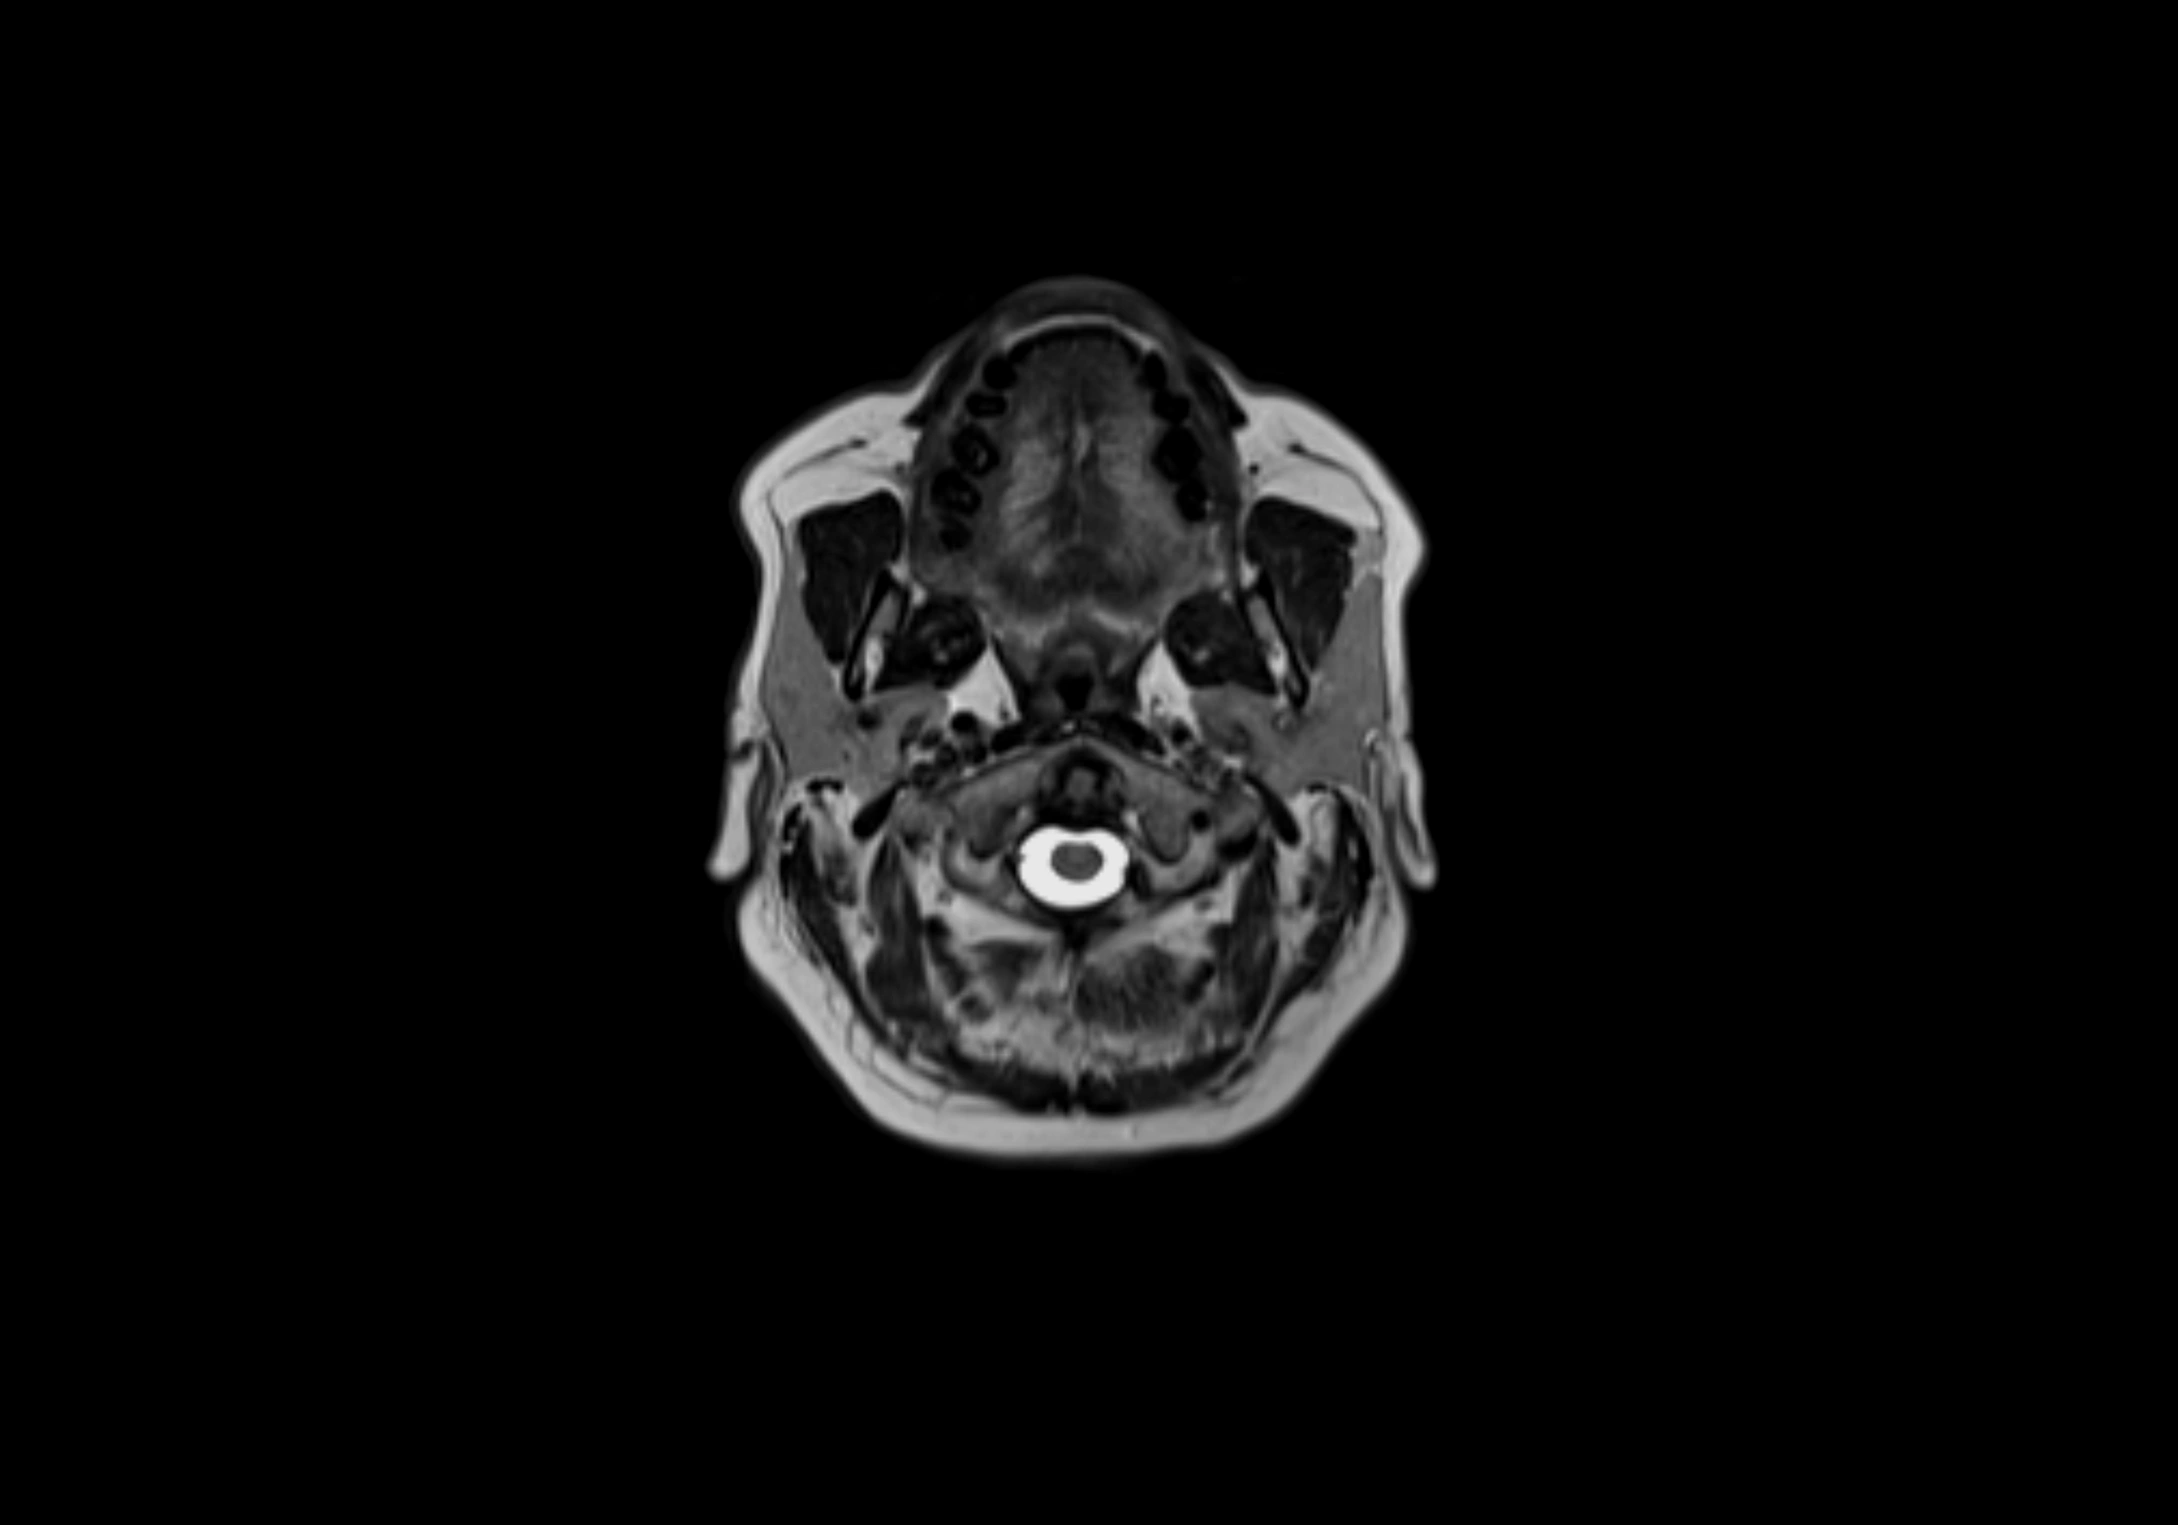

MRI images

image